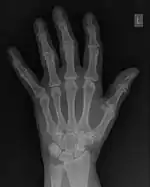

1.23: A profile plot for the yellow line indicated in the radiograph.

The conventional way of interpreting radiographic images in medicine is to regard them as representations of human anatomy. In the mathematical analysis of these images, however, we can interpret them as fluctuations of signal amplitude in space, as demonstrated in Figure 1.23.

FFTs can also be calculated in two-dimensions to give results such as those in Figure 1.27. Since Fourier analysis generates results in terms of both positive and negative spatial frequencies, these can be plotted in the form of a 2D image so that the maximum frequency lies at the origin and those for the horizontal and vertical directions are shown increasing towards that origin. The modulation at different spatial frequencies is represented using a grey-scale. Low frequency bands can be seen along the horizontal axis in the figure, for example, representing the horizontal periodicity of image data from the fingers, while finer bands along the y-dimension are indicative of a periodicity of image data from the various metacarpophalangeal joints. Higher frequency features can also be seen running diagonally in this 2D-FFT, representative of the trabecular structure of the bones, for example.